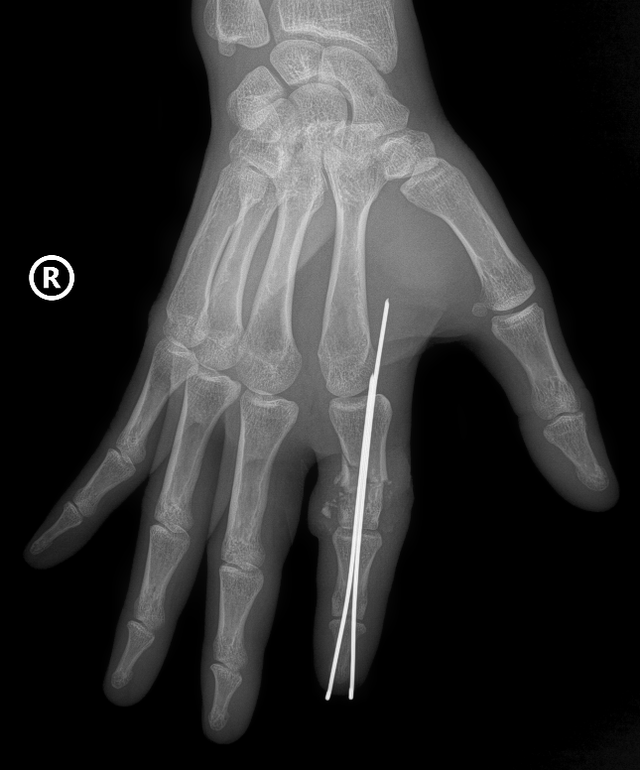

Рентгенівське зображення відрізаного правого вказівного пальця 38-річного моряка, яке знаходять та фіксують за допомогою спеціальної голки.

Дві хірургічні бригади були задіяні паралельно: одна бригада очистила та підготувала відрізаний палець, інша бригада підготувала куксу. Кісточку пальця було встановлено та зафіксовано спеціальною голкою для створення стабільної осі, а також відновлено систему сухожиль та зв'язок.